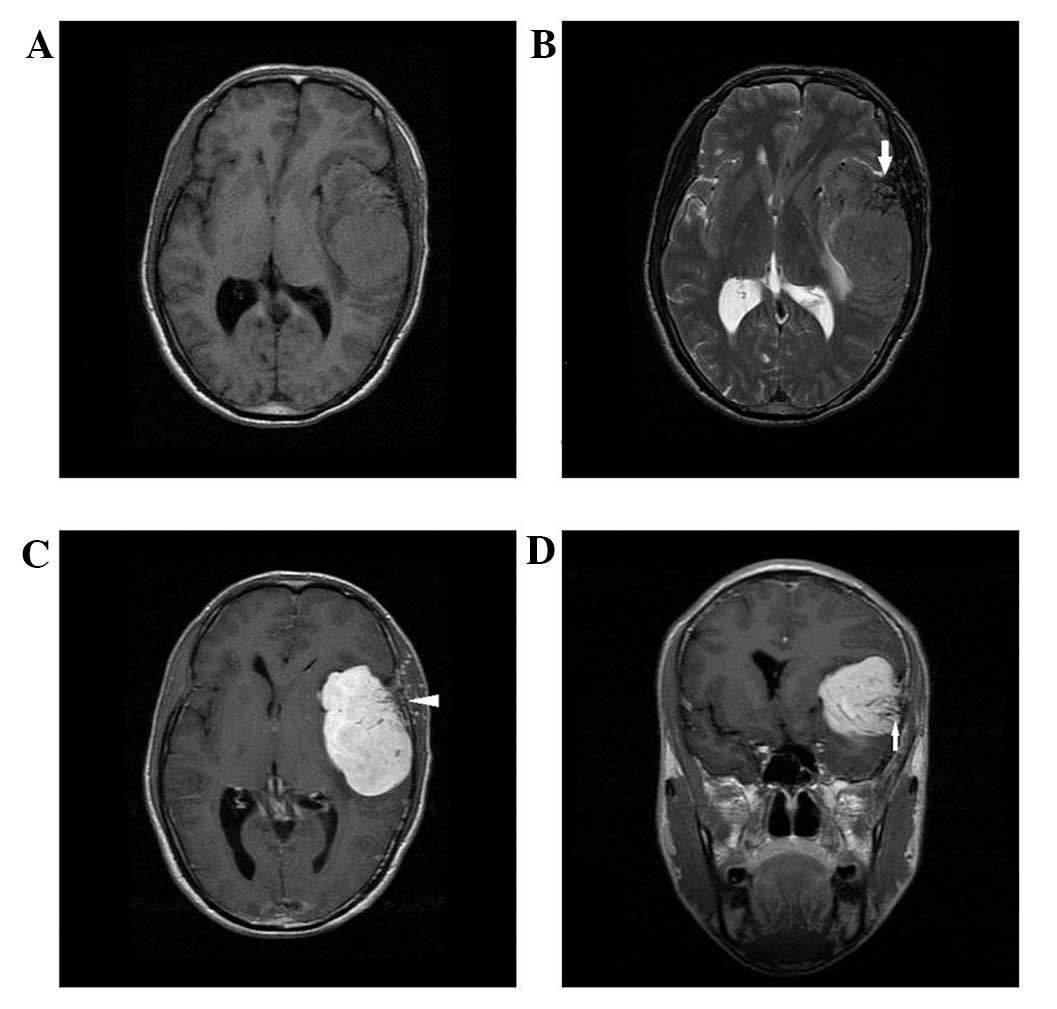

Figure 1

Patient 1. (A) Unenhanced magnetic resonance imaging scan reveals a heterogeneous iso-signal intensity mass in the right occipital region with a well-defined border. (B) The lesion has a marginally long T2 signal with certain intratumoral vessels (arrow), and peritumoral brain edema may be observed. (C) Enhanced scan demonstrates that the mass was markedly heterogeneously enhanced. (D) Cystic degeneration, necrosis and flow void are visible.

All cases were misdiagnosed as meningioma prior to surgery. MRI revealed that all five cases had a single lesion (in four cases located above the tentorium cerebelli; in one case located under the tentorium cerebelli). The lesions were lobular, measuring 3.0 to 7.5 cm with an iso-intense signal in T1WI and a slightly long signal in T2WI on the unenhanced MRI scan (Figs. 1–5). Four cases presented with a cross-midline growth pattern (Figs. 1, 3–5) and one case presented with a cross-lobe growth pattern (Fig. 2). One case exhibited dilatation of the lateral ventricle as the tumor compressed the fourth ventricle (Fig. 5). The adjacent bone was destroyed in one case (Fig. 2). Following injection of Gd-DTPA, no cases were found to exhibit the dural tail sign. Heterogeneous enhancement was observed in all cases (Figs. 1–5). Cystic degeneration, necrosis as well as flow void were observed in all cases (Figs. 1–5). The detailed MRI findings are listed in Table II.

Patient 2. (A) Unenhanced magnetic resonance imaging scan reveals a mass in the left temporal region with heterogeneous iso-signal intensity in the T1-weighted image, and (B) heterogeneous marginally high signal intensity with numerous irregular intratumoral vessels (arrow) in the T2-weighted image. (C) Enhanced scan reveals that the mass is markedly enhanced. The adjacent bone exerts an obstruction effect due to the invasive growth pattern of the tumor (triangle). (D) Coronal reconstruction indicates that the flowing void effect may be visible (arrow).